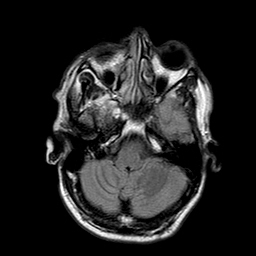

मेरी उम्र 26 साल है मुझे बचपन से लेकर अभी तक किसी भी प्रकार की समस्या नहीं रही है परंतु बीते 2 साल से बाइक के कारण दुर्घटनाग्रस्त हो चुका हूं सन 2015 में जब मेरा एक्सीडेंट हुआ था उस वक्त मेरे उल्टे हाथ की सबसे छोटी उंगली फ्रैक्चर हुई थी उसके ठीक 1 साल बाद 2017 में मार्च 24 को पुनः मेरा बाइक से एक्सीडेंट हो गया. हाथ पैरों मैं चोट आई उल्टे हाथ में काफी सूजन आ गई थी. जब मैं हॉस्पिटल पहुंचा तो वहां सीएमओ के द्वारा X-ray कराने की सलाह दी गई मैंने एक्सरे तुरंत करवाया परंतु सीएमओ के द्वारा एक्सरे में किसी भी प्रकार की फ्रैक्चर का जिक्र नहीं किया उन्होंने यह चीज लिखित में नहीं लिखी थी. मेरे साथ कोई और ना होने के कारण इस चीज पर मैं ध्यान नहीं दे पाया उन्होंने मुझे बताया कि मेरे उल्टे हाथ के टेंडर में चोट आई है जिसके कारण सूजन काफी ज्यादा है और इसको सही होने में 10 दिन से 15 दिन का समय लगता है उसके बाद समस्या ठीक हो जाएगी मुझे लगा कि टंडन में ही अगर प्रॉब्लम है तो धीरे-धीरे ठीक हो जाएगी लेकिन यह समस्या 15 दिन से अधिक होने पर मैं Orthopedics क्टर को दिखाया तब उन्होंने पुनः X-ray कराने की सलाह दी मैंने पुनः एक्सरे कराया और डॉक्टर को दिखाया तब उन्होंने बताया कि फ्रेक्चर इसमें था लेकिन समय पर इसका इलाज ना करने के कारण माल यूनियन हो गया है अब मैं यह जानना चाहता हूं कि इस समस्या के लिए मैं क्या कर सकता हूं और किस प्रकार से समाधान पा सकता हूं क्या भविष्य में इस समस्या के कारण मुझे किसी भी प्रकार की परेशानी आ सकती है अथवा इसके लिए कोई और उपाय करना चाहिए ?

This is My letest left hand Xray 13 Apr 2017